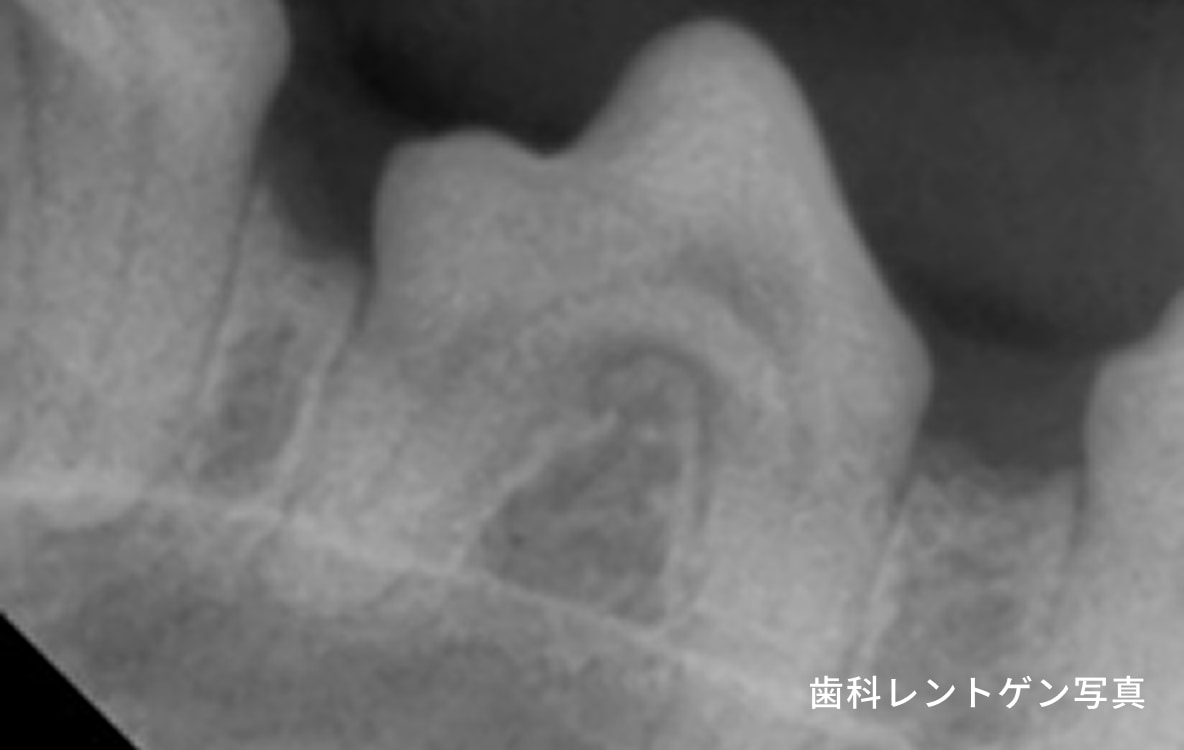

犬の歯周病は、口臭や歯のぐらつきなどから始まり、進行すると歯の痛みや脱落、全身疾患につながるリスクがあります。歯周病はプラークや歯石の蓄積によって引き起こされるもので、これが原因で歯周組織が徐々に破壊されていきます。早期の段階では、炎症や腫れを伴い、犬が口元を気にする仕草が見られることが多いです。しかし、口の痛みがあっても食欲が落ちにくいため、見過ごされやすいので注意が必要です。

治療は内科療法で症状を軽減することはできますが根治は難しく、根本的には全身麻酔下での歯石除去、歯周ポケットのクリーニング、抜歯が必要になることもあります。